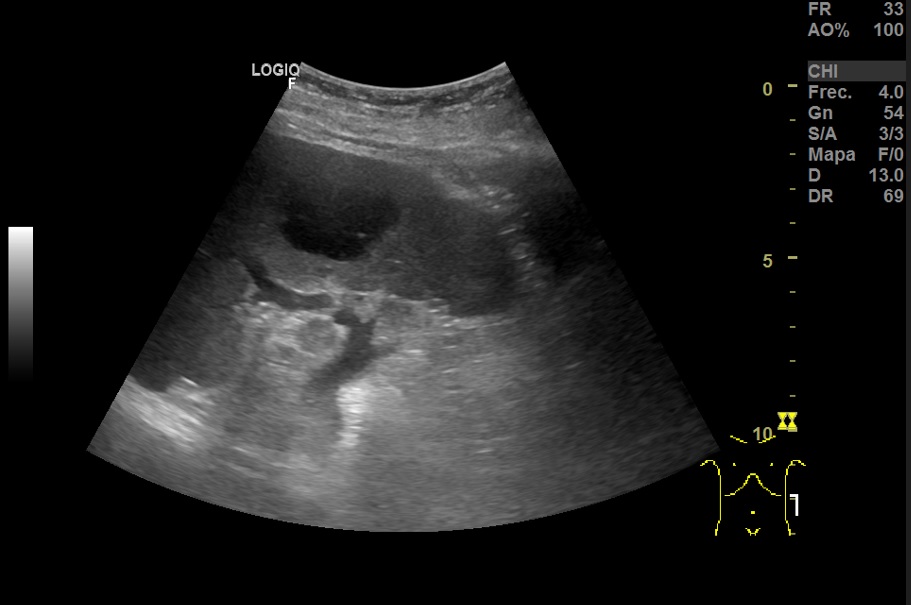

Hallazgos ecográficos

Hallazgos ecográfico: Esplenomegalia y varias lesiones focales hipoecogénicos de diferentes tamaños de bordes bien definidos en el bazo.